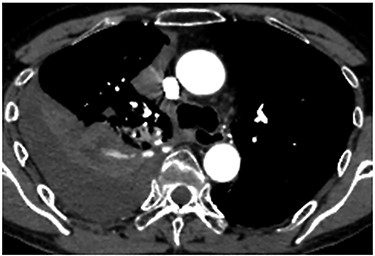

A 60-year-old man underwent right apical and posterior segmentectomies via VATS for early-stage lung cancer. The bronchus and pulmonary parenchyma were divided by endoscopic staples (Echelon®; Ethicon Endo-Surgery). The resected tumour was 1.5 cm in the longest diameter and pathologically diagnosed as Stage IA adenocarcinoma. The patient was discharged uneventfully on eighth day after surgery. Chest radiography revealed no significant findings, and laboratory data were within the normal ranges on the 14th day after discharge at a scheduled visit to the outpatient clinic. However, the patient was transported by ambulance to our hospital owing to a sudden onset of chest pain and dyspnoea on the 32nd day after discharge. He developed hypotension and tachycardia with systolic blood pressure of 50 mmHg and heart rate of 114 beats/min. The haemoglobin concentration level, which had been 12.3 mg/dl on the 14th day after discharge, decreased by 8.7 mg/dl. Chest radiography revealed a massive right pleural fluid, and enhanced computed tomography (CT) showed an extravasation of contrast media near the fifth thoracic vertebra (Fig. 1). The patient was diagnosed with haemothorax and an emergency operation was performed. Thoracoscopic examination revealed massive blood coagulation in the right thoracic cavity, with no adhesions. After removal of the coagulation, continuous active bleeding from the intercostal artery was found near the fifth thoracic vertebra in the vicinity of a stump of the bronchus divided by a staple (Supplementary Video 1). A thoracotomy through the fifth intercostal space was therefore performed to achieve haemostasis, and the bleeding was stopped by suturing using a 4–0 nonabsorbable monofilament ligature. In addition, the bleeding point was covered with a collagen-fibrin patch (Tachosil®). The posterior part of the staple line of the lung parenchyma adjacent to the bleeding point under full inflation was partly exposed, whereas the bronchial stump was covered with lung. Therefore, the scratching created by the staples was assumed to cause haemothorax. The total amount of haematoma in the right thoracic cavity and the intraoperative blood loss was 3980 g. Postoperative CT confirmed that the stapler dividing the lung parenchyma directly faced the bleeding point beside the fifth vertebra (Fig. 2). The patient progressed satisfactorily after the reoperation and was discharged on ninth day after reoperation.

Enhanced chest CT showing an extravasation of contrast media near the fifth thoracic vertebra.